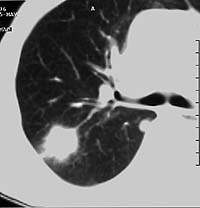

Туберкулема: что это такое и как с ней бороться